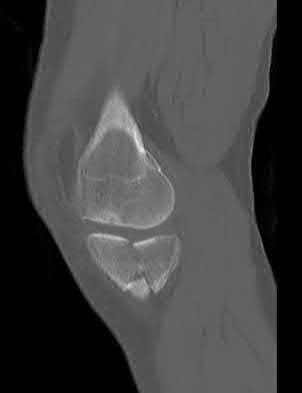

1010) Figures 66a through 66d are the radiographs and CT scans of a 72-year-old woman with osteoporosis who sustained a fall from standing height. She has pain and is unable to bear weight on the right knee. Surgical management is considered. Which of the following best describes the preferred proximal screw fixation construct within a laterally applied buttress plate?

1. 3.5-mm locking screws only

2. 3.5-mm nonlocking screws followed by 3.5-mm locking screws

3. 3.5-mm locking screws followed by 3.5-mm nonlocking screws

4. 6.5-mm fully threaded cancellous screws

5. 6.5-mm partially threaded cancellous screws Corrent answer: 2

Displaced split depression fractures of the lateral tibial plateau require articular surface elevation, restoration of anatomic plateau width, and sustained elevation of the reduced articular components. This is accomplished by introducing nonlocking lag screws first to compress and narrow the lateral rim thus restoring plateau width. The introduction of locking screws first would disallow compression and accordingly prevent reduction of the lateral rim.

Locking screws are inserted after the lag screws if the bone is osteoporotic to maintain articular elevation. Several biomechanical studies have demonstrated

inferior performance of large implants (6.5-mm screws and 4.5-mm plates) with regard to sustaining joint surface elevation.